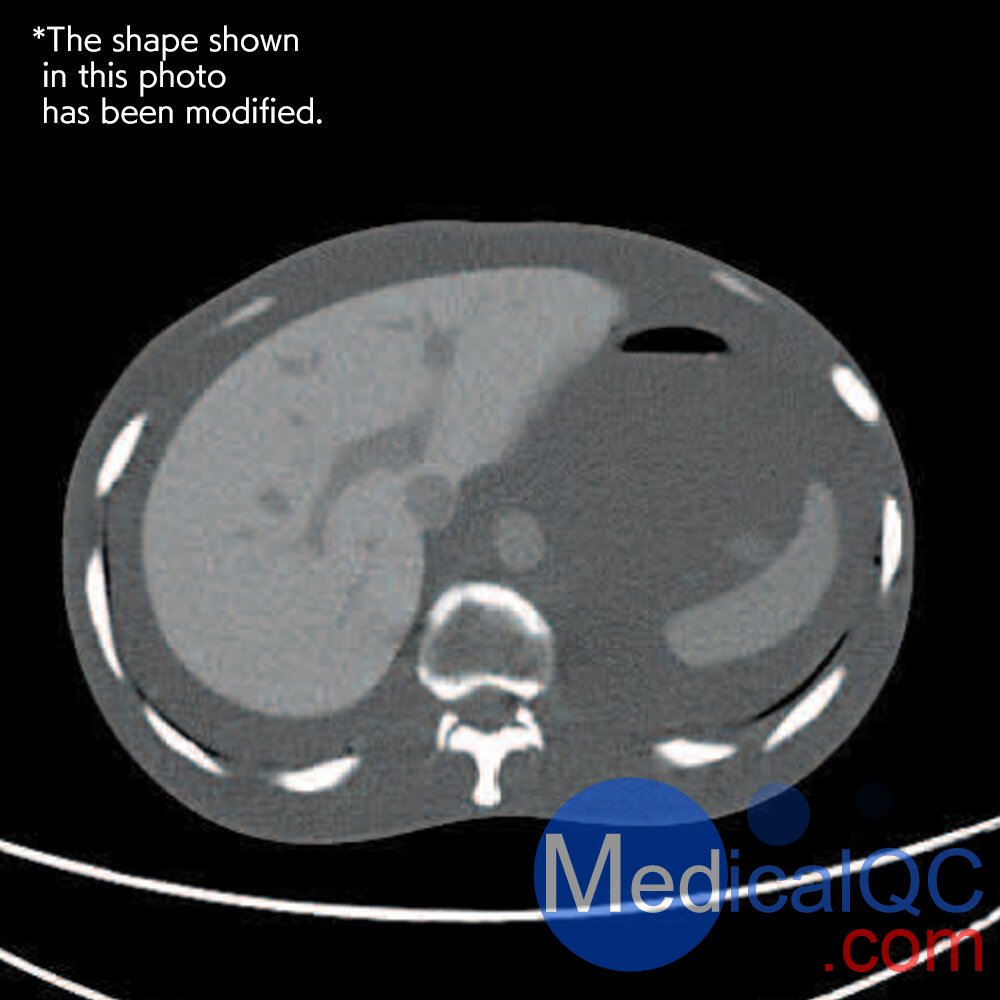

CTU-41 CT躯干模体,PH-4 CT躯干模型,CT人体躯干模型PH-4成像效果:

CTU-41 CT躯干模体,PH-4 CT躯干模型,CT人体躯干模型PH-4成像效果  CTU-41 CT躯干模体,PH-4 CT躯干模型,CT人体躯干模型PH-4成像效果